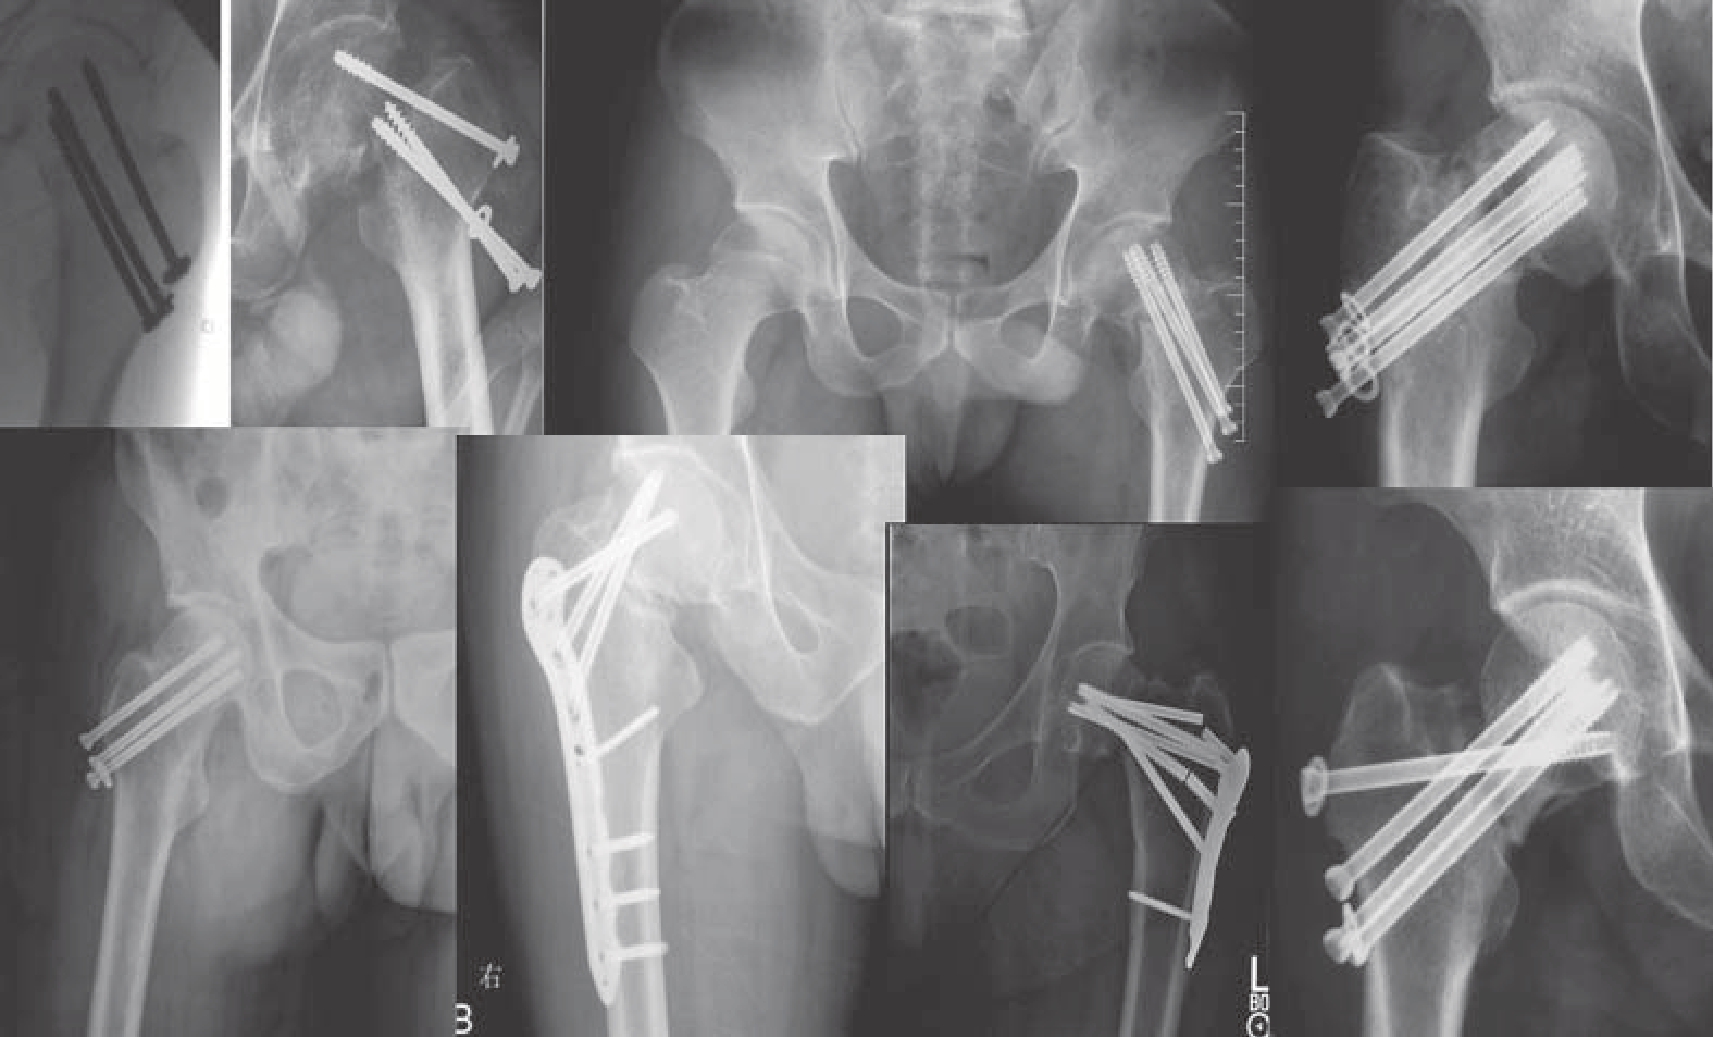

图9—3 股骨颈骨折内固定失效病例汇总

目前,临床上治疗青壮年股骨颈骨折最常用的内固定植入物主要包括:PLCS和动力髋螺钉(dynamic hip screw,DHS)。这两种内植物最主要的固定机制是在骨折断端提供加压(一期)和滑动(二期),使得内植物和骨折断端共同分担应力(loading bearing)。

采用PLCS治疗青壮年股骨颈骨折通常采用3枚直径为6.5~8.0 mm的空心螺钉,以倒三角和正三角构型植入。3枚螺钉植入的部位对于骨折愈合和防止内翻塌陷是非常重要的。一般建议,螺钉应该在股骨颈内尽可能分散植入,远端螺钉沿着股骨距,近端螺钉植入时在侧位片上尽量沿后侧股骨距或皮质植入。这种植入构型被证实可以减少骨不连、畸形愈合、内植物切出以及内固定失效的风险。这种固定方法的优点包括:沿预先植入的导针植入更精准、费用低、骨量丢失少、可微创经皮植入等;但这种固定也存在一些劣势:包括对骨折断面的压缩缺乏控制、无法提供角稳定固定;使用拉力螺钉固定的另一个缺点是一旦这些拉力螺钉没有平行植入,则会对骨折断端的加压产生不利影响。

DHS联合或不联合一枚抗旋螺钉也是固定股骨颈骨折的另一个经典的固定方法。滑动的髋螺钉可以对骨折断端进行加压以及滑动,以促进骨折的愈合。它可以被理解为一块可滑动的接骨板,而非稳定固定角度的螺钉。对股骨颈骨折的固定稳定有限,特别是旋转稳定性,所以常规推荐联合一枚抗旋螺钉。由于缺乏内侧支撑,有时内翻塌陷无法避免,螺钉可能从上方切出。直径较大的滑动螺钉植入时的扭矩较大易使骨折移位。此外,直径较大的滑动螺钉会对股骨头骨质和血运造成破坏,而且常有侧方的接骨板较厚引起的软组织刺激。尽管DHS的侧方钢板钉孔数量可以为2~20孔,但有研究发现使用2孔侧方钢板和4孔侧方钢板在模拟的生理载荷循环中的强度和失效载荷是相同的。髋螺钉植入的位置也曾被广泛研究,目前建议植入的位置应该使尖顶距(tip-apex distance,TAD)<25 mm,以降低髋螺钉切除的风险。如果不使用抗旋螺钉而单独使用DHS时,由于只有一枚髋螺钉,也就避免了使用PLCS时必须做到的平行植入。